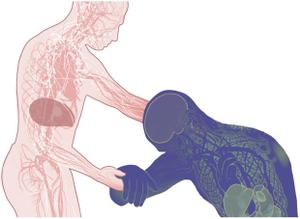

ویروس ابولا، قبل از اینکه از نابودی آبشاری سیستم ایمنی بدن، عروق خونی و اندام های حیاتی را آغاز کند، می تواند برای بیش از یک هفته در بدن پنهان بماند.

استراتژی تهاجم سلول

۱. ویروس به سطح سلول می چسبد، در آن وارد شده و توسط غشای سلولی احاطه می شود.

۲. پروتئین هایی که جهش سلول را پوشش می دهند غشا را باز کرده و اجازه می دهند RNA ویروس وارد سلول شود و شروع به همانندسازی کند.

۳. نحوه خروج از سلول به طور کامل درک و شناخته نشده است، اما به نظر می رسد که ذرات ویروس در سطح سلول جمع شده و بیرون می آیند و ممکن است با یک پاکت میزبان خارج شوند.

مرحله حمله

ویروس به سلول های ایمنی در جریان خون حمله می کند، و عفونت را به کبد، طحال و گره های لنفاوی انتقال می دهد. ابولا از انتشار اینترفرون، یک پروتئین ساخته شده توسط سلول های ایمنی برای مبارزه با ویروس، جلوگیری می کند.

سلول های ایمنی آلوده از طریق جریان خون یا مجراهای لنفی به دیگر بافت ها و اندام ها، به خارج از طحال و گره های لنفاوی، انتقال می یابند.

مشکل در جریان خون

پروتئین های منتشر شده توسط سلول های ایمنی، التهاب گسترده ای را ایجاد می کنند. این التهاب می تواند به پوشش بافت رگ های خونی آسیب رسانده و باعث نشت آنها شود.

هنگامی که سلول های ایمنی شناخته شده به عنوان ماکروفاژها توسط ابولا مورد حمله قرار می گیرند، پروتئین ها را آزاد می کنند که این موضوع باعث انعقاد در جریان خون و انسداد جریان خون در بافت هایی از جمله کبد، مغز و کلیه ها می شود. هنگامی که سلول های قرمز خون درون عروق کوچکی که از لخته پر شده اند حرکت می کنند، از هم گسسته شده و طحال از رگ های خونی شکسته شده، پوشیده می شود.

هنگامی که سلول ها در کبد از بین می روند، خون توانایی طبیعی خود را برای لخته شدن از دست می دهد و هر گونه خونریزی داخلی یا خارجی را تشدید می کند.

اختلالات چند سیستمی

• ابولا یا توسط سلول های آلوده به ویروس یا با پاسخ التهابی شدید بدن، به بسیاری از بافت ها آسیب می رساند.

• اختلال غدد آدرنال، منجر به فشار خون پایین خطرناک و کاهش توانایی تولید هورمون های استروئیدی می شود.

• به بافت های همبند بدن، که نقش سلول های پوشاننده برای حفره ها و سطوح بدن را دارند، حمله می شود.

• نارسایی کبد و کلیه رخ می دهد.

• پانکراس آلوده می تواند منجر به درد شدید شکم شود.

• آسیب روده باعث اسهال و کاهش آب بدن می شود.

مایع در مغز تجمع می یابد. تشنج باعث گسترش خون عفونی و سایر مایعات بدن بیمار می شود.